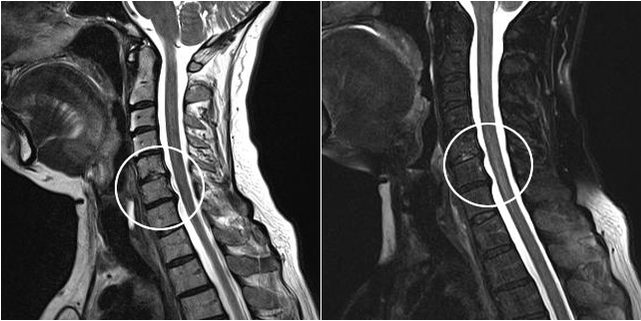

Šiuolaikiniai diagnostikos metodai apima MRT ir KT, kurie leidžia tiksliausiai ištirti kremzlės ir kaulinio audinio sunaikinimo procesus. Taip pat naudojant šią techniką patogu diagnozuoti išvaržas ir kitus minkštųjų audinių defektus šalia ligos šaltinio.